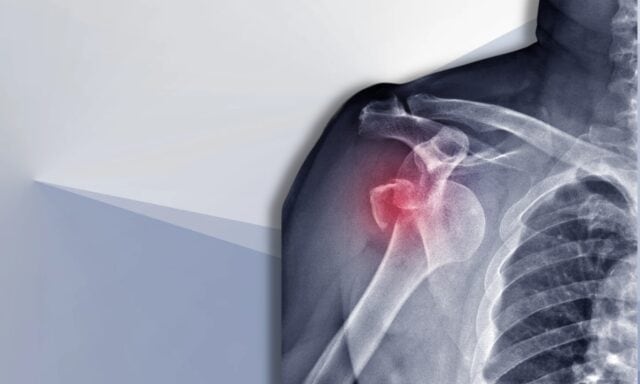

U ovoj epizodi pričat ćemo o svemu što se tiče nestabilnosti ramena. Naučit ćete više o Stanmore klasifikaciji i strukturnim oštećenjima nakon iščašenja. Razgovarat ćemo o tipičnom pacijentu s nestabilnošću ramena i kako izgleda proces pregleda. Dotaknut ćemo se obrazaca aktivacije mišića, kirurgije i kako bi uopće moglo izgledati fizioterapijsko liječenje pacijenta s nestabilnošću ramena. Stoga svakako poslušajte cijelu epizodu!